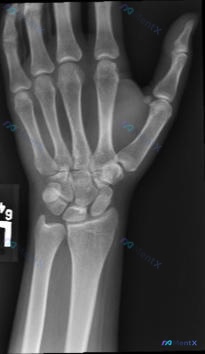

整理了一个很有启发性的运动损伤病例,核心在于「不要被正常的静态X光片带偏」。 --- 病例资料 - 患者:22岁女性体操运动员 - 病史:左手腕疼痛不适1个月,有韧带病史,已接受手腕保守治疗 - 影像(X光正侧位): - 桡骨远端、尺骨远端、腕骨群骨质完整,未见明确骨折线、脱位或骨质改变 - 桡腕关...